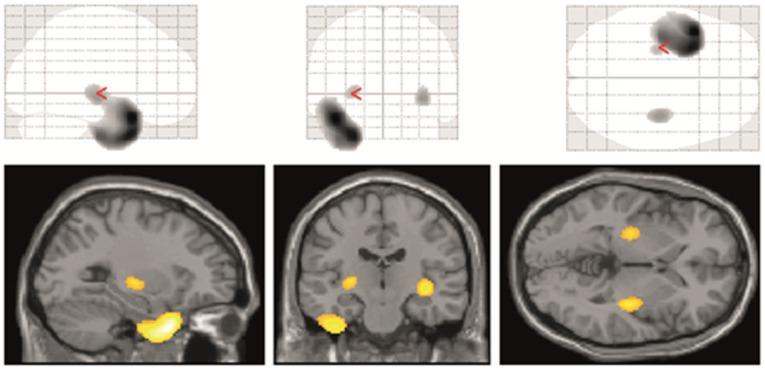

To quantify D2/D3 receptor binding, we studied 21 patients with TLE and hippocampal sclerosis (13 left- and eight right-sided) and 18 controls using PET with the high-affinity dopamine D2/D3-receptor ligand 18F-Fallypride to image striatal and extrastriatal binding. TLE was defined by interictal and ictal video-EEG, MRI and 18F-Fluorodeoxyglucose PET. Voxel-based statistical and regions-of-interest analyses were performed.

RESULTS

18F-Fallypride binding potential was significantly reduced in the affected temporal lobe and bilateral putamen. A positive correlation between age at onset of epilepsy and [18F]FP BPnd (binding potential non-displaceable) in temporal regions on the epileptogenic side was found, as well as a negative correlation between epilepsy duration and [18F]FP BPnd in the temporal pole on the epileptogenic side and a positive correlation between the estimated number of lifetime GTCS and [18F]FP BPnd in the hippocampus on the epileptogenic side.

SIGNIFICANCE

The areas of reduced D2/D3 receptor availability correspond to "the irritative zone" surrounding the epileptogenic area. Moreover, reduced D2/D3 receptor availability was detectable in the basal ganglia, which are suspected to be involved in a control circuit for epileptic seizures. The correlational analysis additionally suggests that increased epilepsy duration leads to increasing impairment of the dopaminergic system.